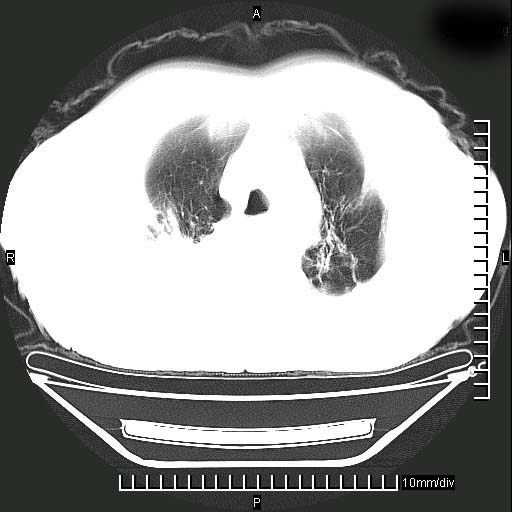

标题: CT24043:胸部增强:男性,60岁

既往肺结核,近10几天,咳嗽,咳痰,右侧胸痛,疼痛较明显,右上肺斑块考虑结核灶胸膜粘连,增强,可惜动脉期没有定好,未见强化,可延迟4分后又见较明显强化,中心见低密度影,如果说结核是边缘强化,可这个灶强化的面积挺大的,让人很挠头。

1)两肺继发性肺结核。2)右侧胸膜增厚+少量胸腔积液。